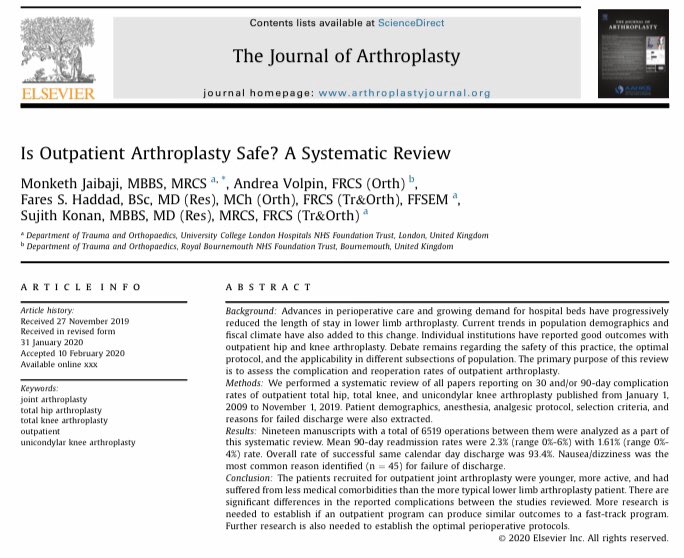

Is outpatient arthroplasty safe? Monketh Jaibaji one of our MSc students published an excellent systematic review in The Journal of Arthroplasty assessing the complication and reoperation rates of outpatient arthroplasty. pubmed.ncbi.nlm.nih.gov/32192837/ #Orthotwitter #MScUCL